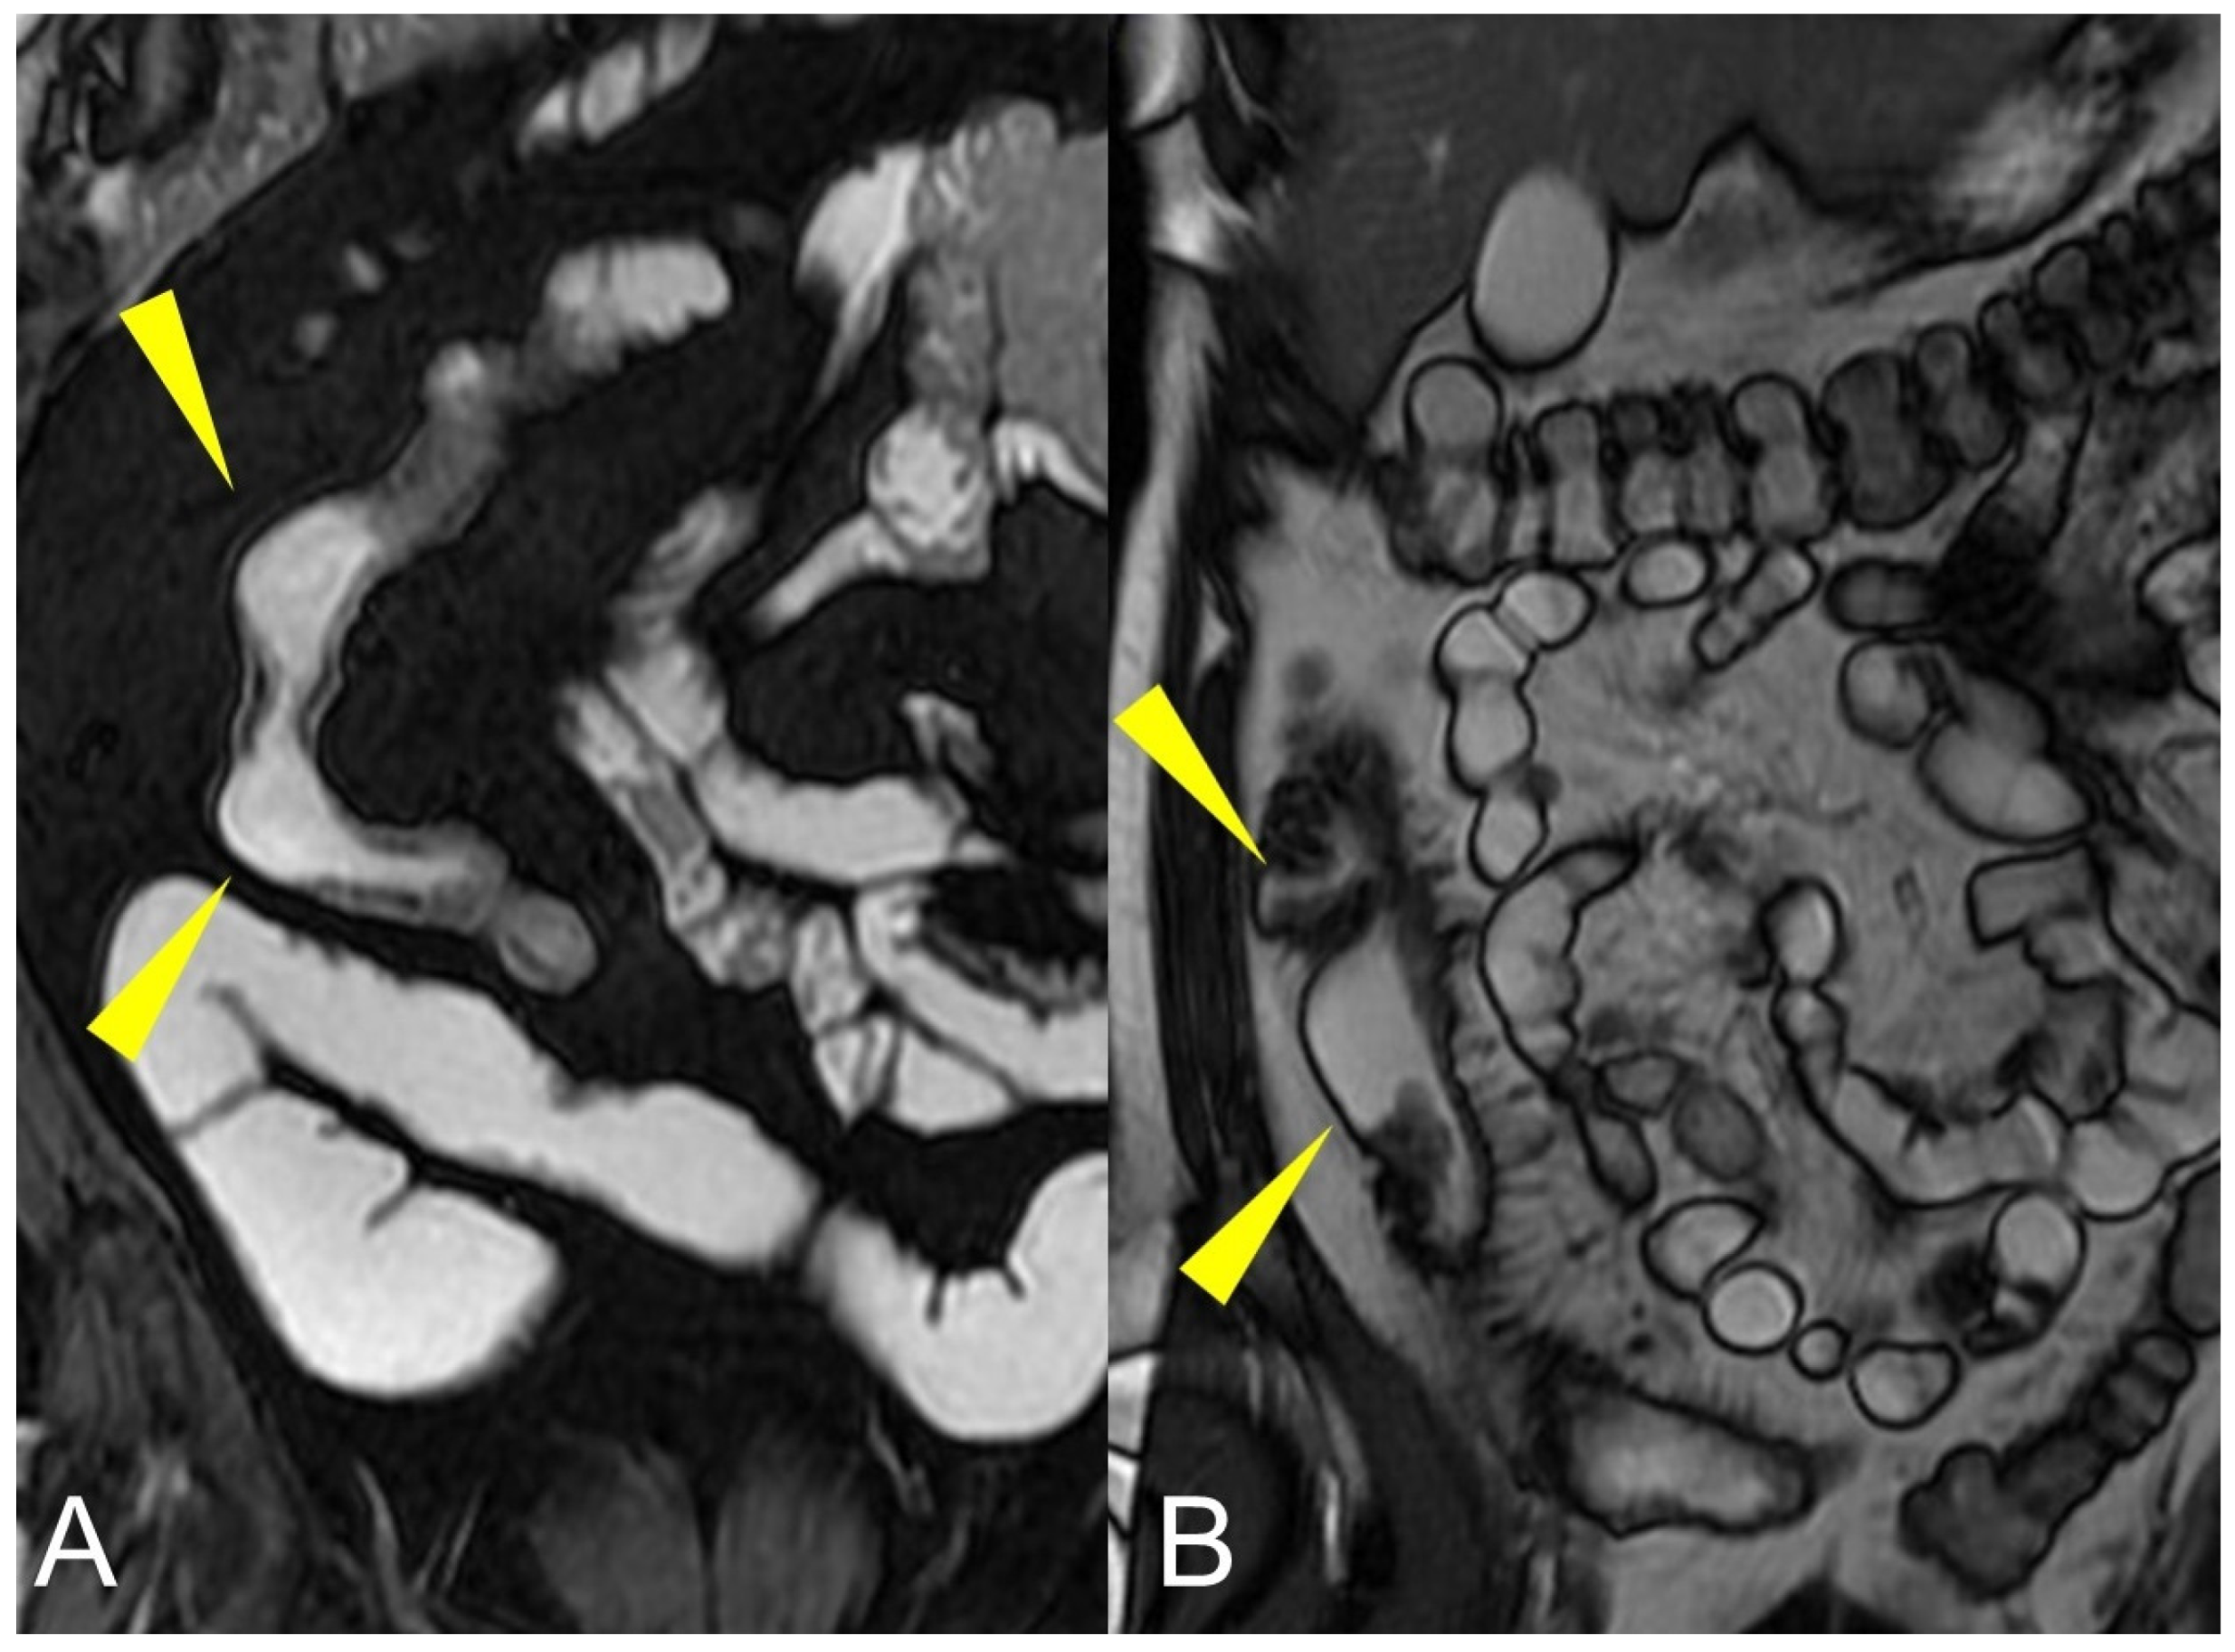

Figure 9.

Pathological junctions of intestinal segments through enteroenteric fistulas, which represents internal fistulas that connect intestinal segments such as ileo-sigmoidal (A) and ileo-colic (B).